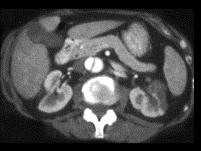

男,54岁,请根据所示图像,选择最可能诊断 ( )A、左侧肾梗死B、主动脉夹层C、左侧肾囊肿D、左侧肾积水E、左侧肾脓肿

问题 男,54岁,请根据所示图像,选择最可能诊断 ( )

选项 A、左侧肾梗死 B、主动脉夹层 C、左侧肾囊肿 D、左侧肾积水 E、左侧肾脓肿

答案 AB